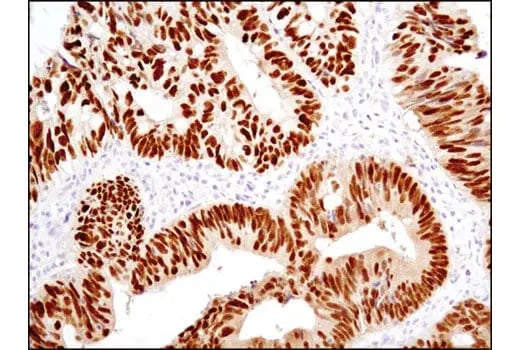

IHC analysis of paraffin-embedded human endometrioid adenocarcinoma using ZEB1 (E2G6Y) Rabbit Monoclonal Antibody #70512.